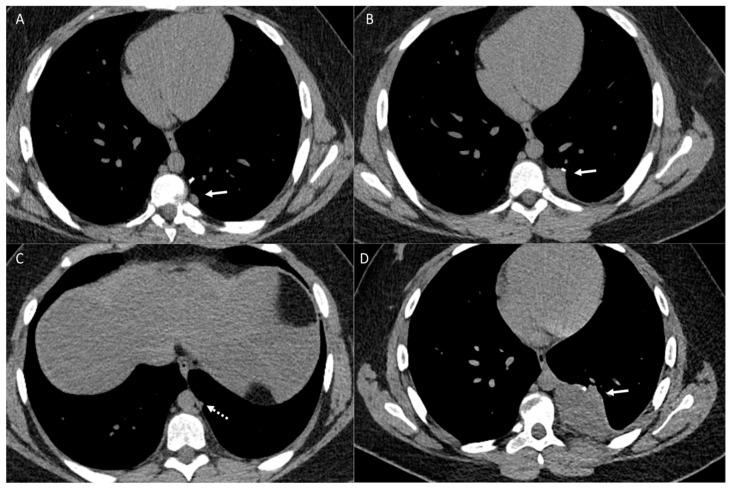

Osteosarcoma, a primary bone malignancy in children and adolescents, frequently metastasizes to the lungs, contributing significantly to morbidity and mortality. At diagnosis, 15-20% of patients present with detectable lung metastases. Chest computed tomography (CT) is vital for the early detection and monitoring of these metastases. Lung involvement typically presents as multiple nodules of varying sizes and can include atypical features such as cavitation, cystic lesions, ground-glass halos, intravascular tumor thrombi, and endobronchial disease. Pleural metastasis often occurs alongside pulmonary disease, and complications like spontaneous pneumothorax may arise. Additional findings may include thoracic lymphadenopathy, cardiac tumor thrombus, and chest wall deposits. Familiarity with these imaging patterns is essential for radiologists to ensure timely diagnosis and effective management. This review highlights the critical role of chest CT in detecting and characterizing osteosarcoma metastasis.

骨肉瘤是儿童和青少年常见的原发性骨恶性肿瘤,常转移至肺部,对发病率和死亡率有显著影响。在诊断时,15%至20%的患者出现可检测到的肺转移。胸部计算机断层扫描(CT)对于这些转移灶的早期检测和监测至关重要。肺部受累通常表现为大小不一的多个结节,可包括一些非典型特征,如空洞形成、囊性病变、磨玻璃晕、血管内肿瘤血栓和支气管内病变。胸膜转移常与肺部疾病同时发生,可能出现自发性气胸等并发症。其他表现可能包括胸内淋巴结肿大、心脏肿瘤血栓和胸壁转移灶。放射科医生熟悉这些影像学表现对于确保及时诊断和有效治疗至关重要。本综述强调了胸部CT在检测和鉴别骨肉瘤转移方面的关键作用。